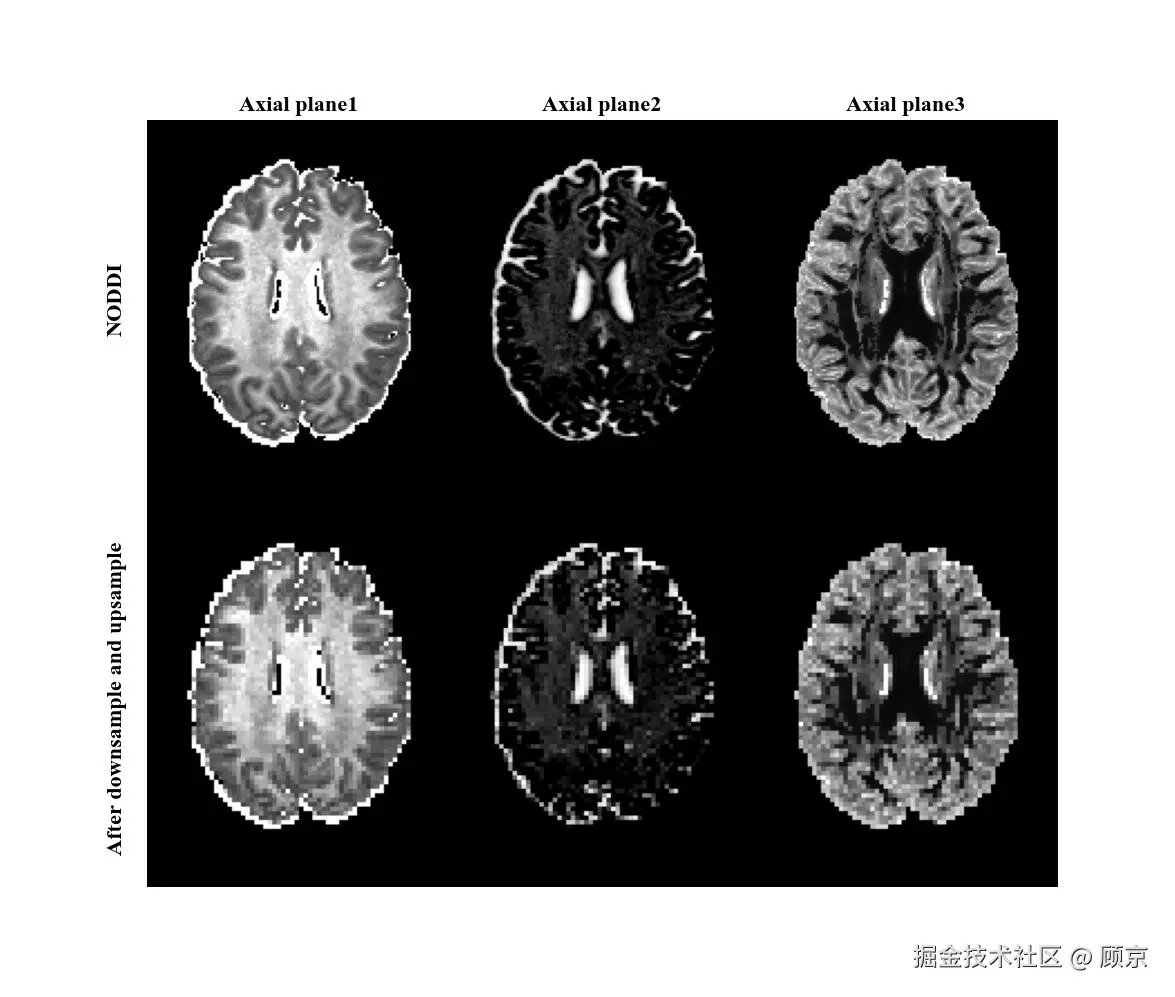

下上采样

由于下采样会损失图像细节,而普通基于插值的上采样是无法生成细节的,先下采样再上采样便成为了一种图像降级方法,如图3所示。

dusample.jpeg

图3 下上采样方式